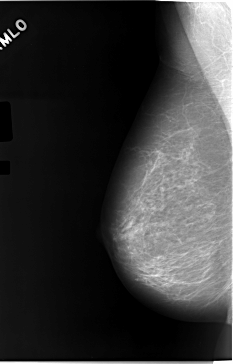

C_0046_1.LEFT_MLO